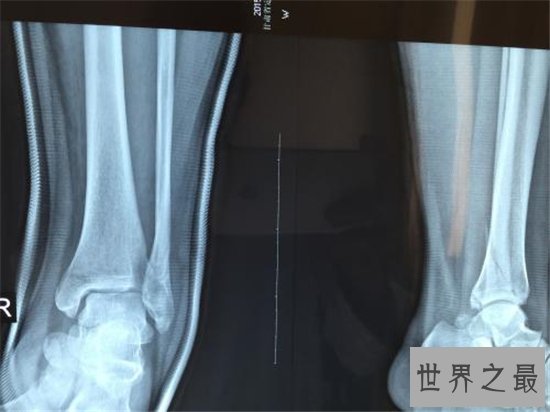

2、踝关节骨折

踝关节就是我们通常说的“脚踝”,是人体骨骼中相当脆弱的一节,也是人体活动必不可少甚至可以说是至关重要的一环。且踝关节属于比较容易受伤的一个部位,一旦踝关节骨折,我们就几乎会陷入无法正常行走乃至不良于行的困难境地。